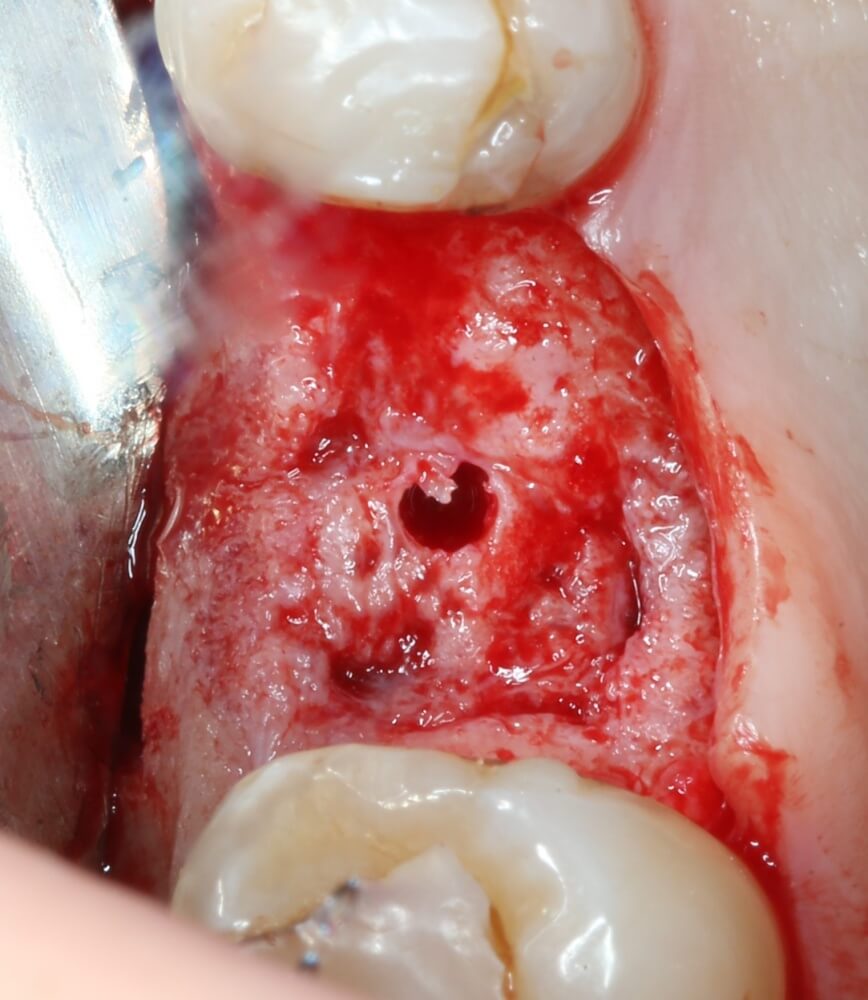

Кортикальная фреза погружается строго до отметки (см выше). В нашем клиническом случае (с синуслифтингом) это особенно важно, чтобы имплантат не улетел в субантральное пространство. Таким образом получаем лунку, полностью конгруэнтную будущему имплантату. Это очень-очень важно:

Если лунка подготовлена правильно, то имплантат проваливается в неё почти полностью: